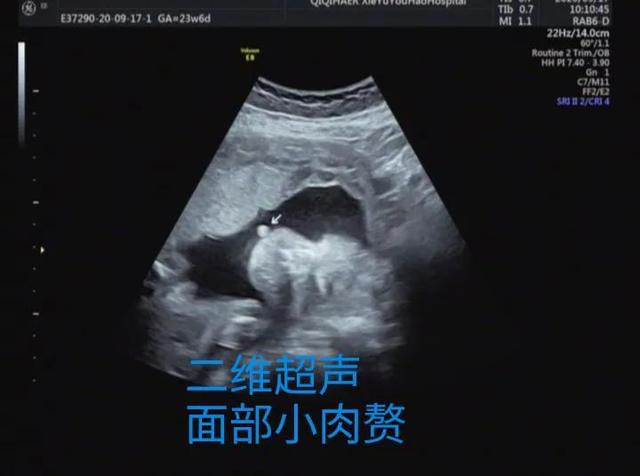

妈妈们更关心的是2D超声和3D超声的区别,简单的科普讲解,超声医生通过多切面和动态2D超声诊断畸形,3D成像只是在必要的时候起到辅助作用。胎儿表面结构的三维图像客观真实。一旦出现胎儿体表畸形,如唇裂、脑膨出、脊柱裂、脐膨出、腹裂、四肢、手脚畸形等,三维影像可以让孕妇及其家属一目了然,便于产科医生或儿科医生根据实际情况提供建议和意见,方便选择下一步的治疗方案。这里有几个小案例,读者可以自己体验一下。

案例1